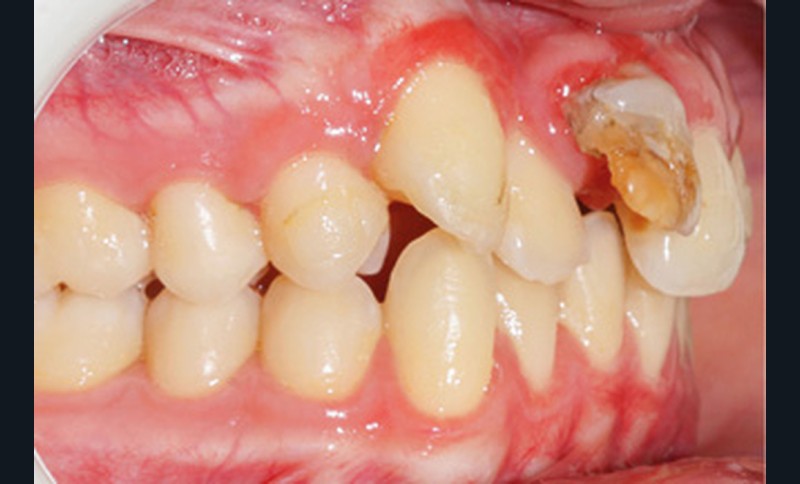

À l’examen clinique, on observe un visage symétrique, et un profil équilibré, avec un léger excès vertical de l’étage inférieur, induisant une incompétence labiale au repos (fig. 1a).

D’un point de vue occlusal, le patient, en denture adulte jeune stable, présente une classe II d’Angle bilatérale de 4 mm, associée à un encombrement maxillaire de 5 mm et mandibulaire de 2 mm. La face mésiale de 21 est centrée avec le plan sagittal médian, la non-concordance des médianes incisives est d’origine mandibulaire (déviation de la médiane mandibulaire vers la gauche) (fig. 1b-d).

Son incisive centrale supérieure droite (11) présente un défaut de structure amélaire sévère, compromettant une technique restaurative pérenne a minima. L’examen de la panoramique (fig. 1e) et de la radiographie rétroalvéolaire de 11 (fig. 1f) objective une fracture coronaire verticale, ainsi qu’une racine grêle et courbe, peut-être en rapport avec un ancien traumatisme [1]. Le rapport couronne clinique/racine clinique est défavorable.